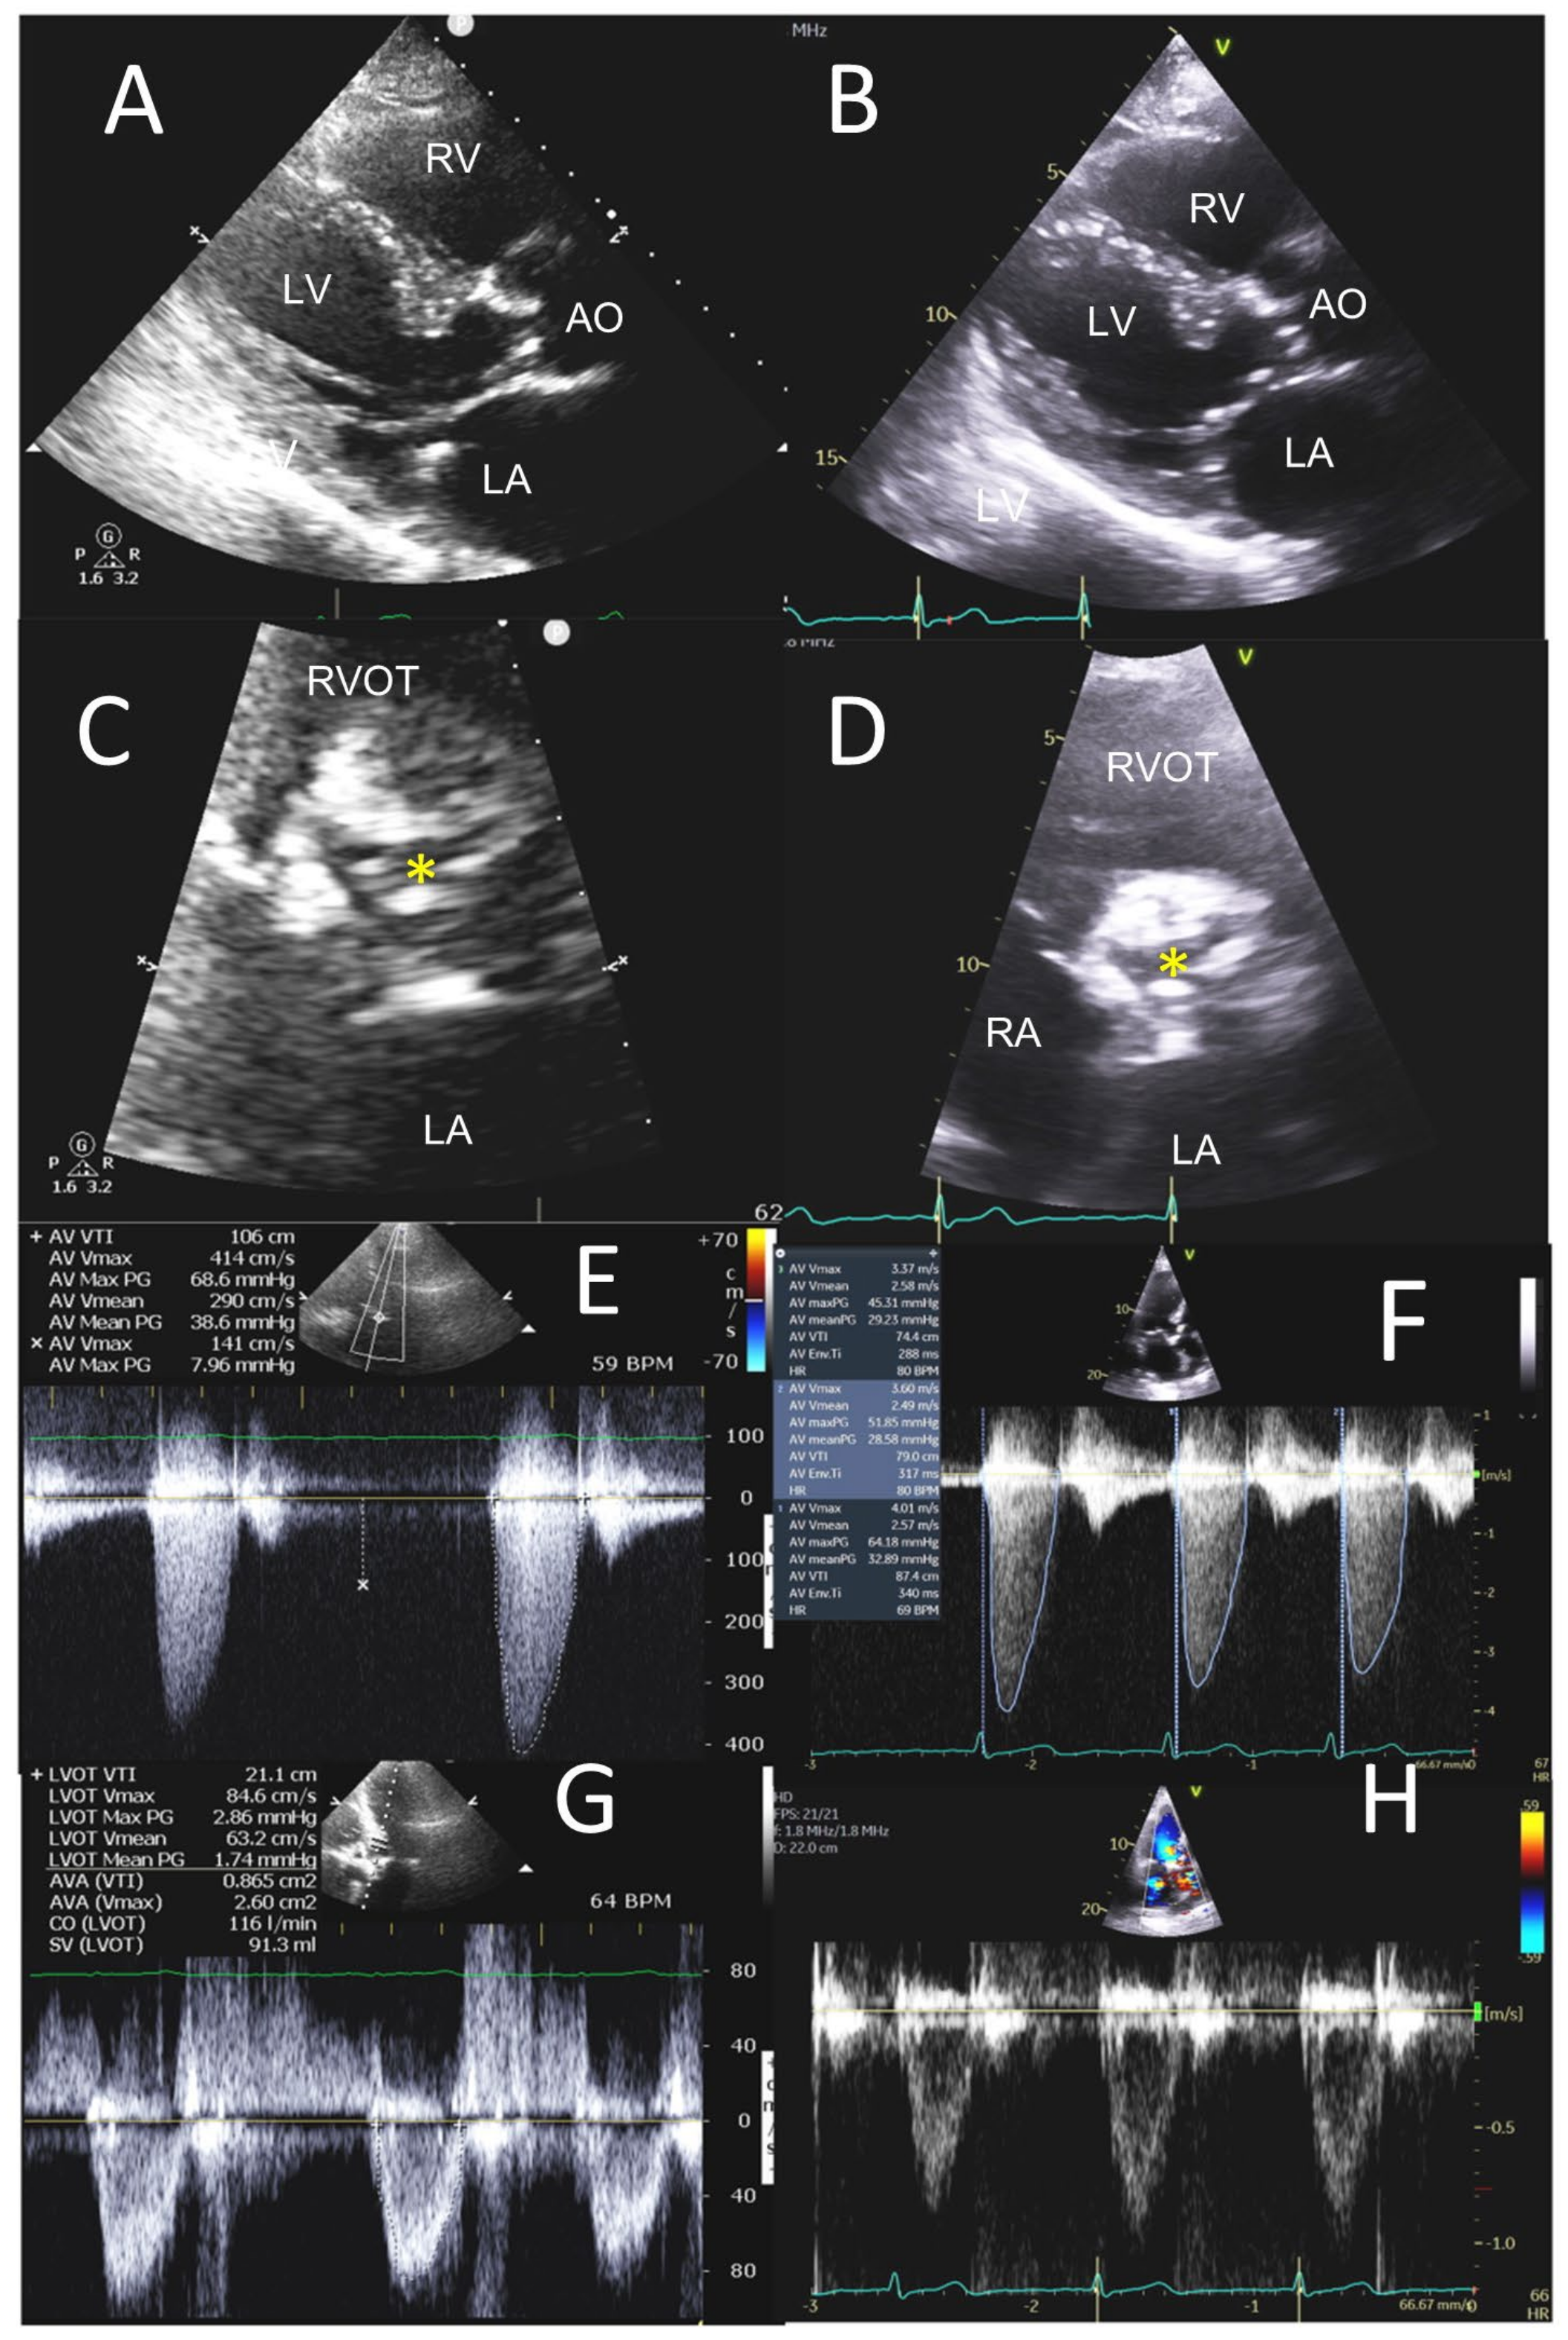

3.3. ≥Moderate Valvular Stenosis

4.1.2. POCUS with Portable Small Ultrasound Machines